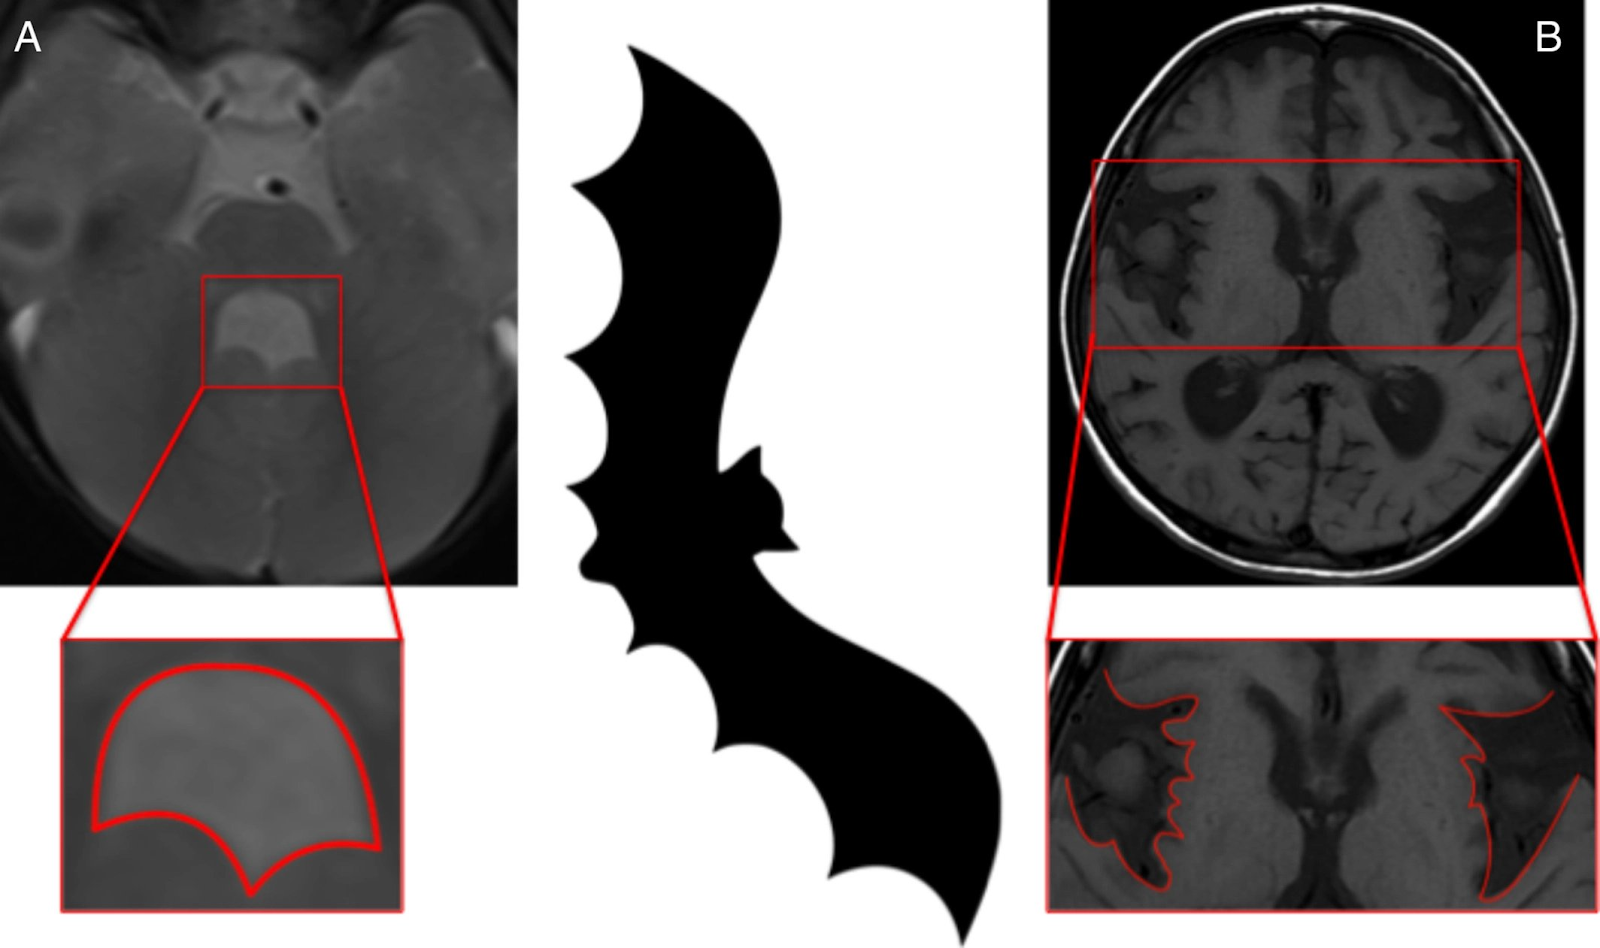

11)

Bat Wing Fourth Ventricle

Clinical Correlate: Joubert Syndrome